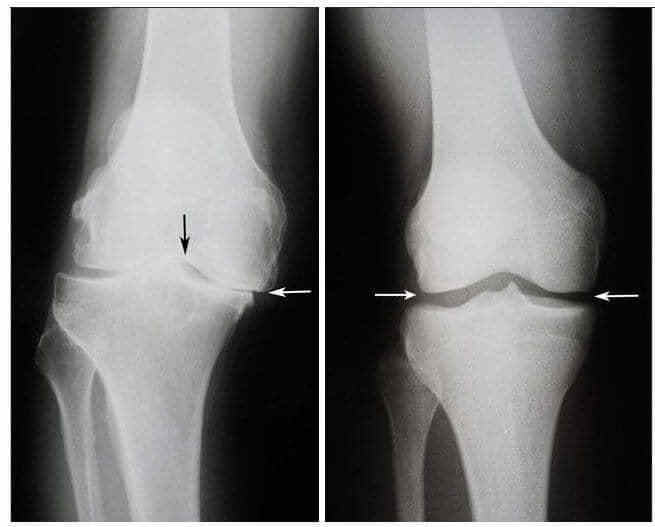

Знімок колінного суглоба Валентини до і після лікування

Ліворуч: Знімок до лікування - хрящова тканина повністю зруйнована. Рекомендація лікаря – операція та заміна суглоба.

Праворуч: Знімок після лікування капсулами OsteoFix - суттєве поліпшення стану суглоба.